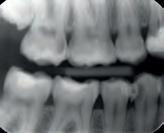

Röntgenonderzoek (foto 2)

• Radiolucentie rondom de coronale mesiale pulpa

• Forse halo-vormige peri-apicale radiolucentie

• De tracing van zowel de pocket als de fistel verlopen naar het interradiculaire gebied.